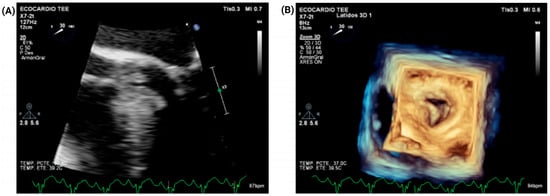

Combined Fixed and Dynamic Left Ventricular Outflow Tract Obstruction in Hypertrophic Cardiomyopathy Due to a Coexisting Subaortic Membrane: A Case Report

Introduction: Hypertrophic cardiomyopathy (HCM) is a common myocardial disease worldwide and is associated with heart failure symptoms and sudden cardiac death. In a subset of patients, it may produce dynamic left ventricular outflow tract obstruction (LVOTO) and systolic anterior motion (SAM)-related mitral valve dysfunction through drag forces and altered mitral–septal geometry. In contrast, subaortic stenosis caused by a subaortic membrane is an uncommon congenital lesion that may lead to fixed subvalvular LVOTO in adulthood. The coexistence of these entities is rare and can substantially complicate diagnosis and management. Case presentation: A 51-year-old woman with HCM, paroxysmal atrial fibrillation, and heart failure presented with acute decompensation and cardiogenic shock. After initial hemodynamic stabilization and cardioversion for atrial fibrillation with rapid ventricular response, multimodality imaging with transthoracic and transesophageal echocardiography, coronary computed tomography angiography, and cardiac magnetic resonance demonstrated dual LVOTO, with a dynamic component related to HCM/SAM physiology and a fixed component caused by an elongated subaortic membrane, accompanied by severe SAM-related mitral regurgitation. Echocardiography showed a resting peak LVOT gradient of 49 mmHg, increasing to 85 mmHg with the Valsalva maneuver. After exclusion of obstructive coronary artery disease and evaluation for selected phenocopies, the patient underwent septal myectomy, subaortic membrane resection, and adjunctive mitral valve plication. Early postoperative echocardiography showed reduction in the maximum provoked LVOT gradient to 38 mmHg and improvement of mitral regurgitation from severe to mild. At 3-month follow-up, she remained in sinus rhythm, improved to New York Heart Association functional class II, and had no documented readmissions for heart failure. Conclusions: Combined fixed and dynamic LVOTO due to concomitant subaortic membrane and HCM is exceedingly rare. Accurate diagnosis requires a high index of suspicion and a multimodality imaging strategy to define the obstructive mechanisms and support mechanism-based surgical management and avoid incomplete treatment when a coexisting fixed lesion is present. Full article

Figure 1